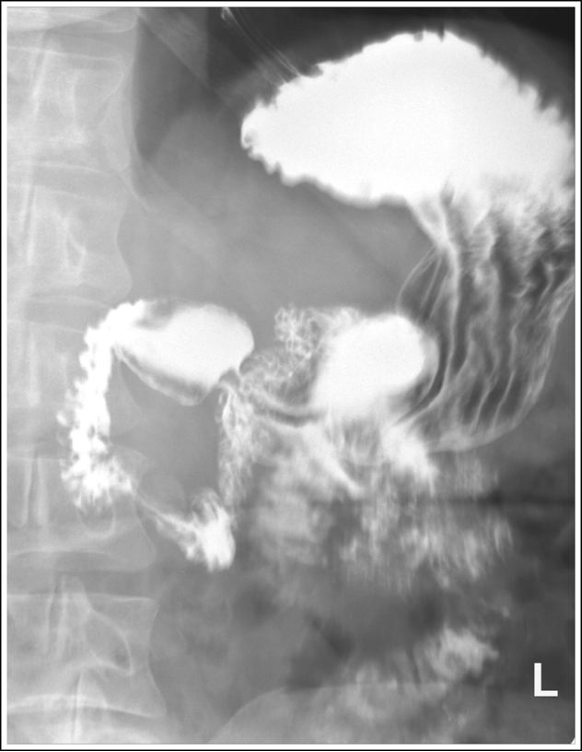

Oblique stomach with bony cortices are sharp and the gastric and intestines are blurry. Peristaltic activity of the stomach and small intestines